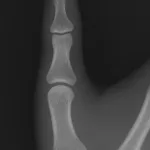

右股関節のX線写真を確認.

体内の固定材料(Femoral Neck System)にズレはなく, 大腿骨頚部の短縮も認めません.

骨折線は不明瞭になりつつあり, 骨癒合は順調と判断しました.

そのため, 本日からは右脚に体重の約半分(おおよそ30 kg)の荷重をかけることにしました.